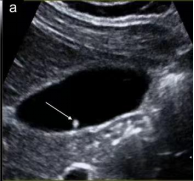

首选检查为超声检查,该检查无创、方便易行、廉价,对息肉的形态、血流有很好的判断,尤其对胆囊胆固醇沉积症、胆囊腺肌症等有独特的影像显示,是常规体检、随访的必备检查。

• 如超声检查探及血流信号,则肿瘤性息肉可能性大,不论息肉大小,应及时行胆囊切除术。